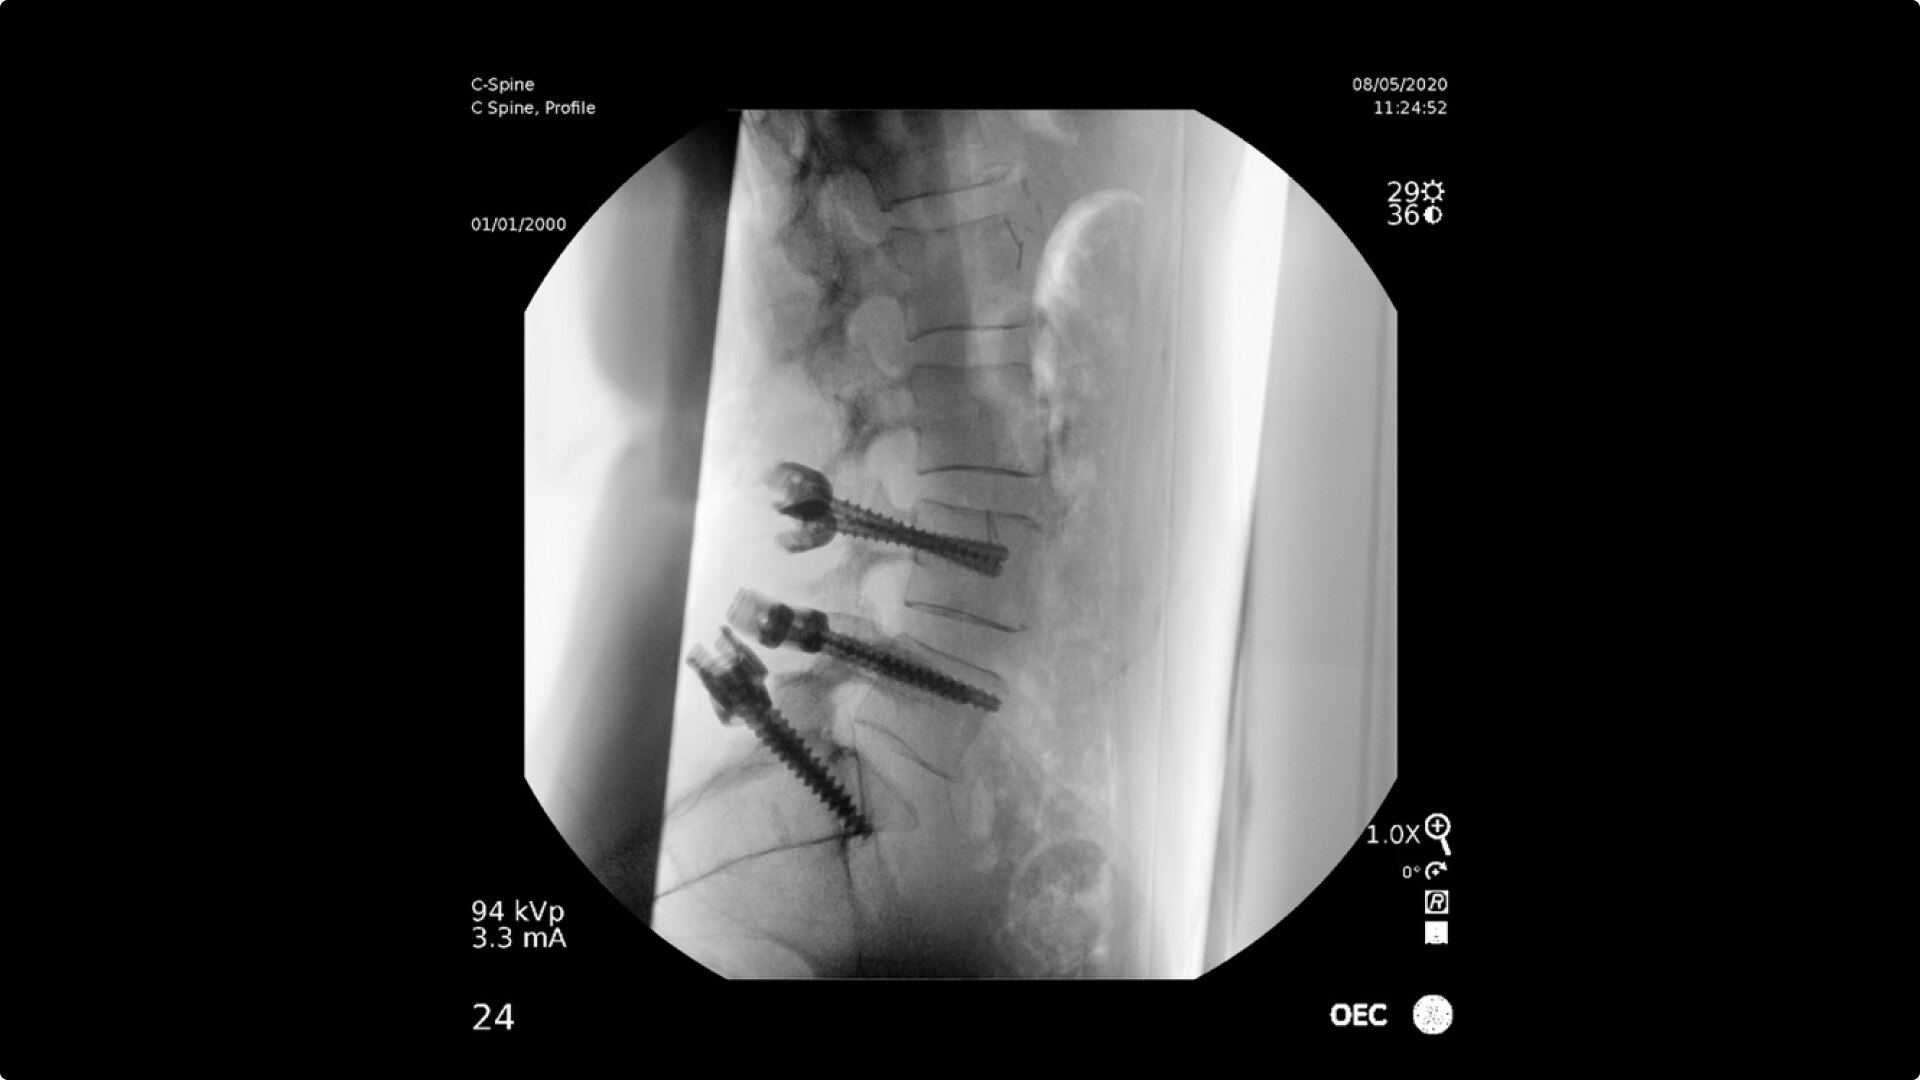

Pain management imaging you need

Pain Management procedures require powerful imaging systems.

OEC C-arms perform imaging in a variety of procedures such as:

• Steroid injections

• Radiofrequency treatments

• Contrast media injections

• Cervical spine pain management

• Thoracolumbar procedures